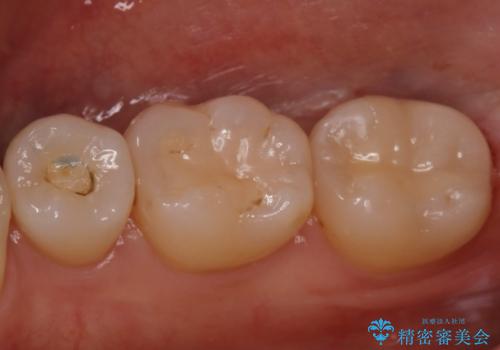

昔の被せ物が取れてしまった セラミックアンレーで治療

- 昔に治療した金属のかぶせものが取れてしまい来院されました。他院にて応急処置がされており、レントゲンなどで現状を把握した後、切削量が比較的少なく短期間で終了するセラミックアンレーにて治療いたしました。

経過良好で噛み合わせなども問題なく、前の被せ物より綺麗な被せ物がセットされ、非常に満足いただけました。